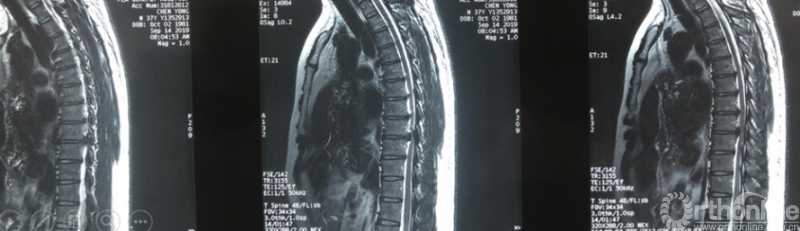

Case5:多节段胸椎后纵韧带钙化可视化治疗

影像学资料

术中资料

同一侧一次两个节段减压,择期对侧进行两个节段减压,两侧腹侧减压范围可达到硬膜囊360度环形减压效果。术后复查硬膜囊环形减压效果。关节突关节破坏较多,需长期佩戴支具固定,保证术后脊柱稳定性。

术后复查资料